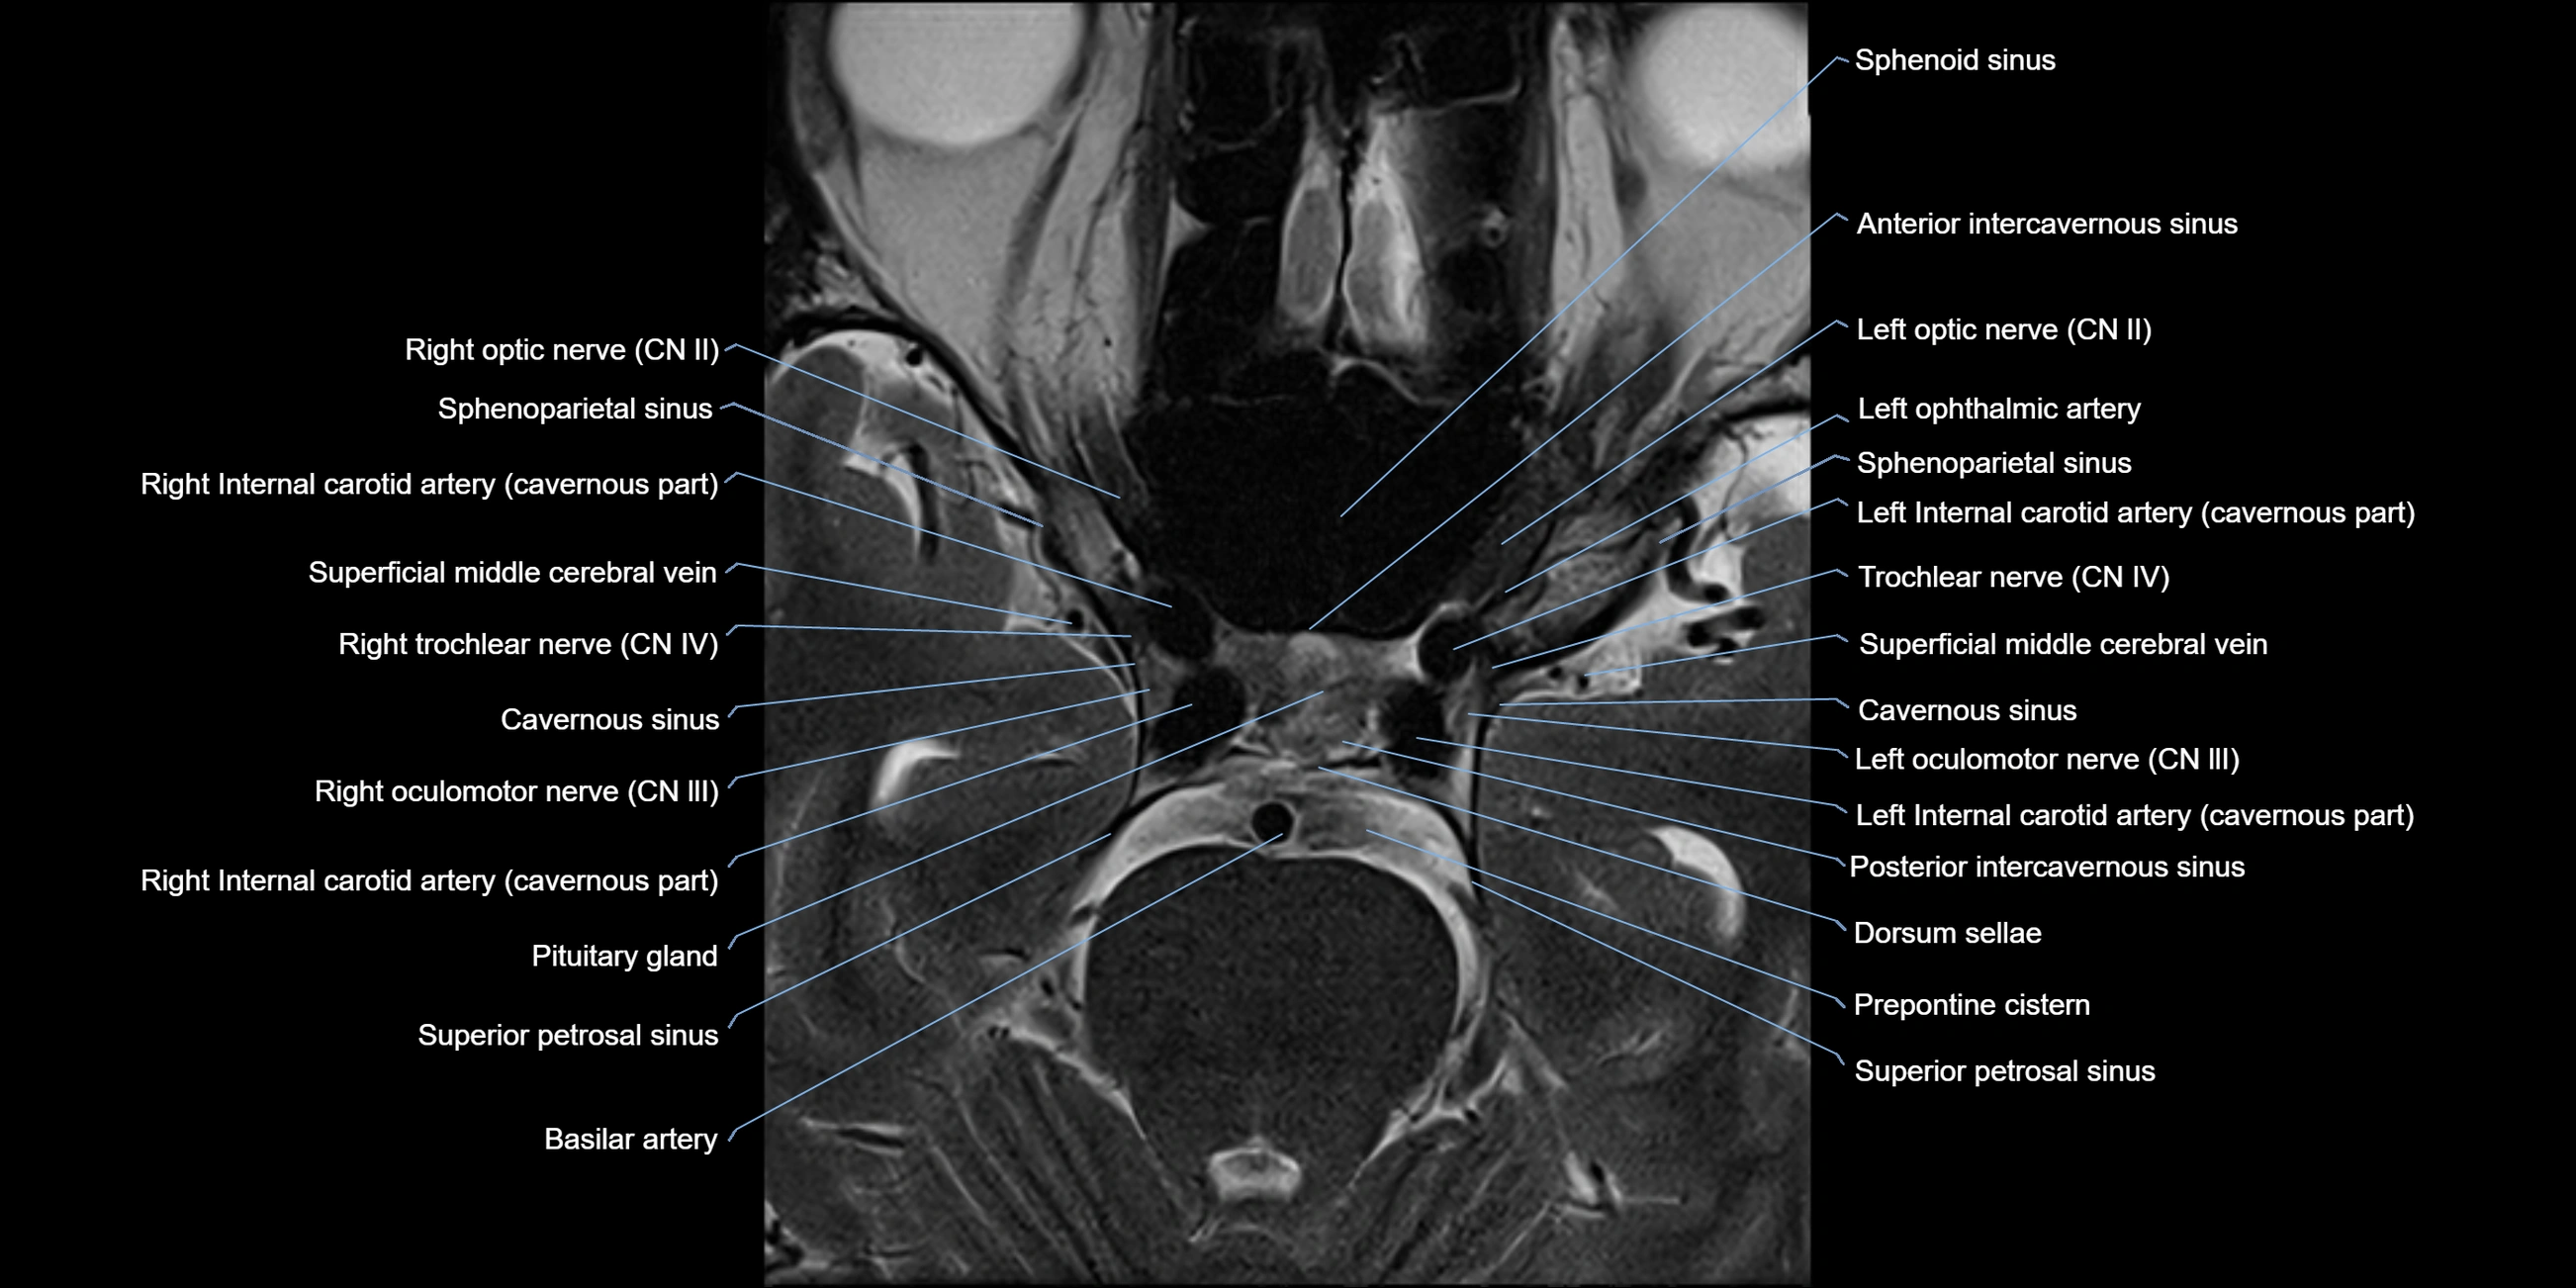

MRI images